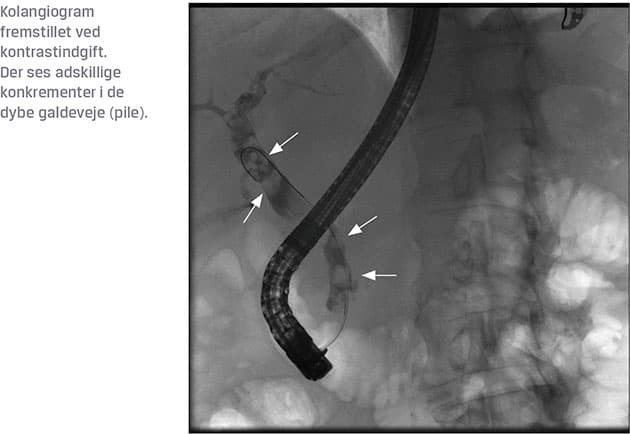

Risikostratificering på baggrund af patientrelaterede risikofaktorer for PEP bør forudgå enhver ERCP, og denne viden sammenholdt med indikationen bør danne grundlag for beslutningen om at udføre ERCP. Ligeledes bør ERCP kun anvendes i terapeutisk øjemed, og billedmodaliteter som endoskopisk ultralydskanning og MR-kolangiopankreatografi bør anvendes, hvis der er tvivl om diagnosen eller om, hvorvidt det er muligt at opnå et gunstigt resultat ved ERCP (Figur 1) [6].